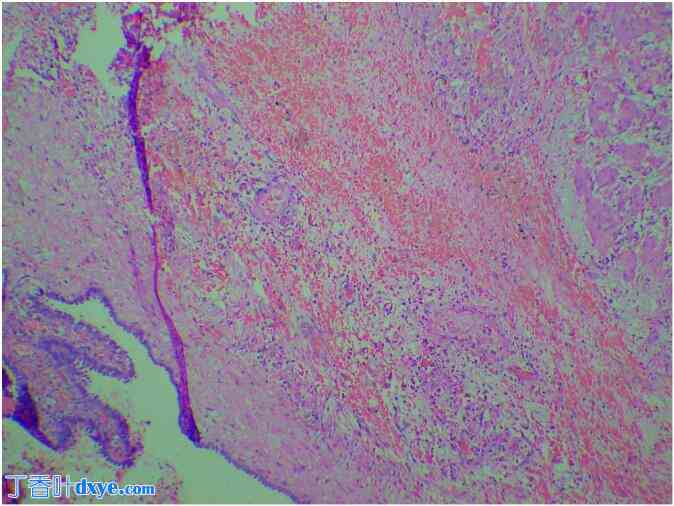

图 4。

4.jpg

标本的组织病理学显示输卵管管腔扩张,皱襞扁平。管壁上有出血灶和出血性坏死。